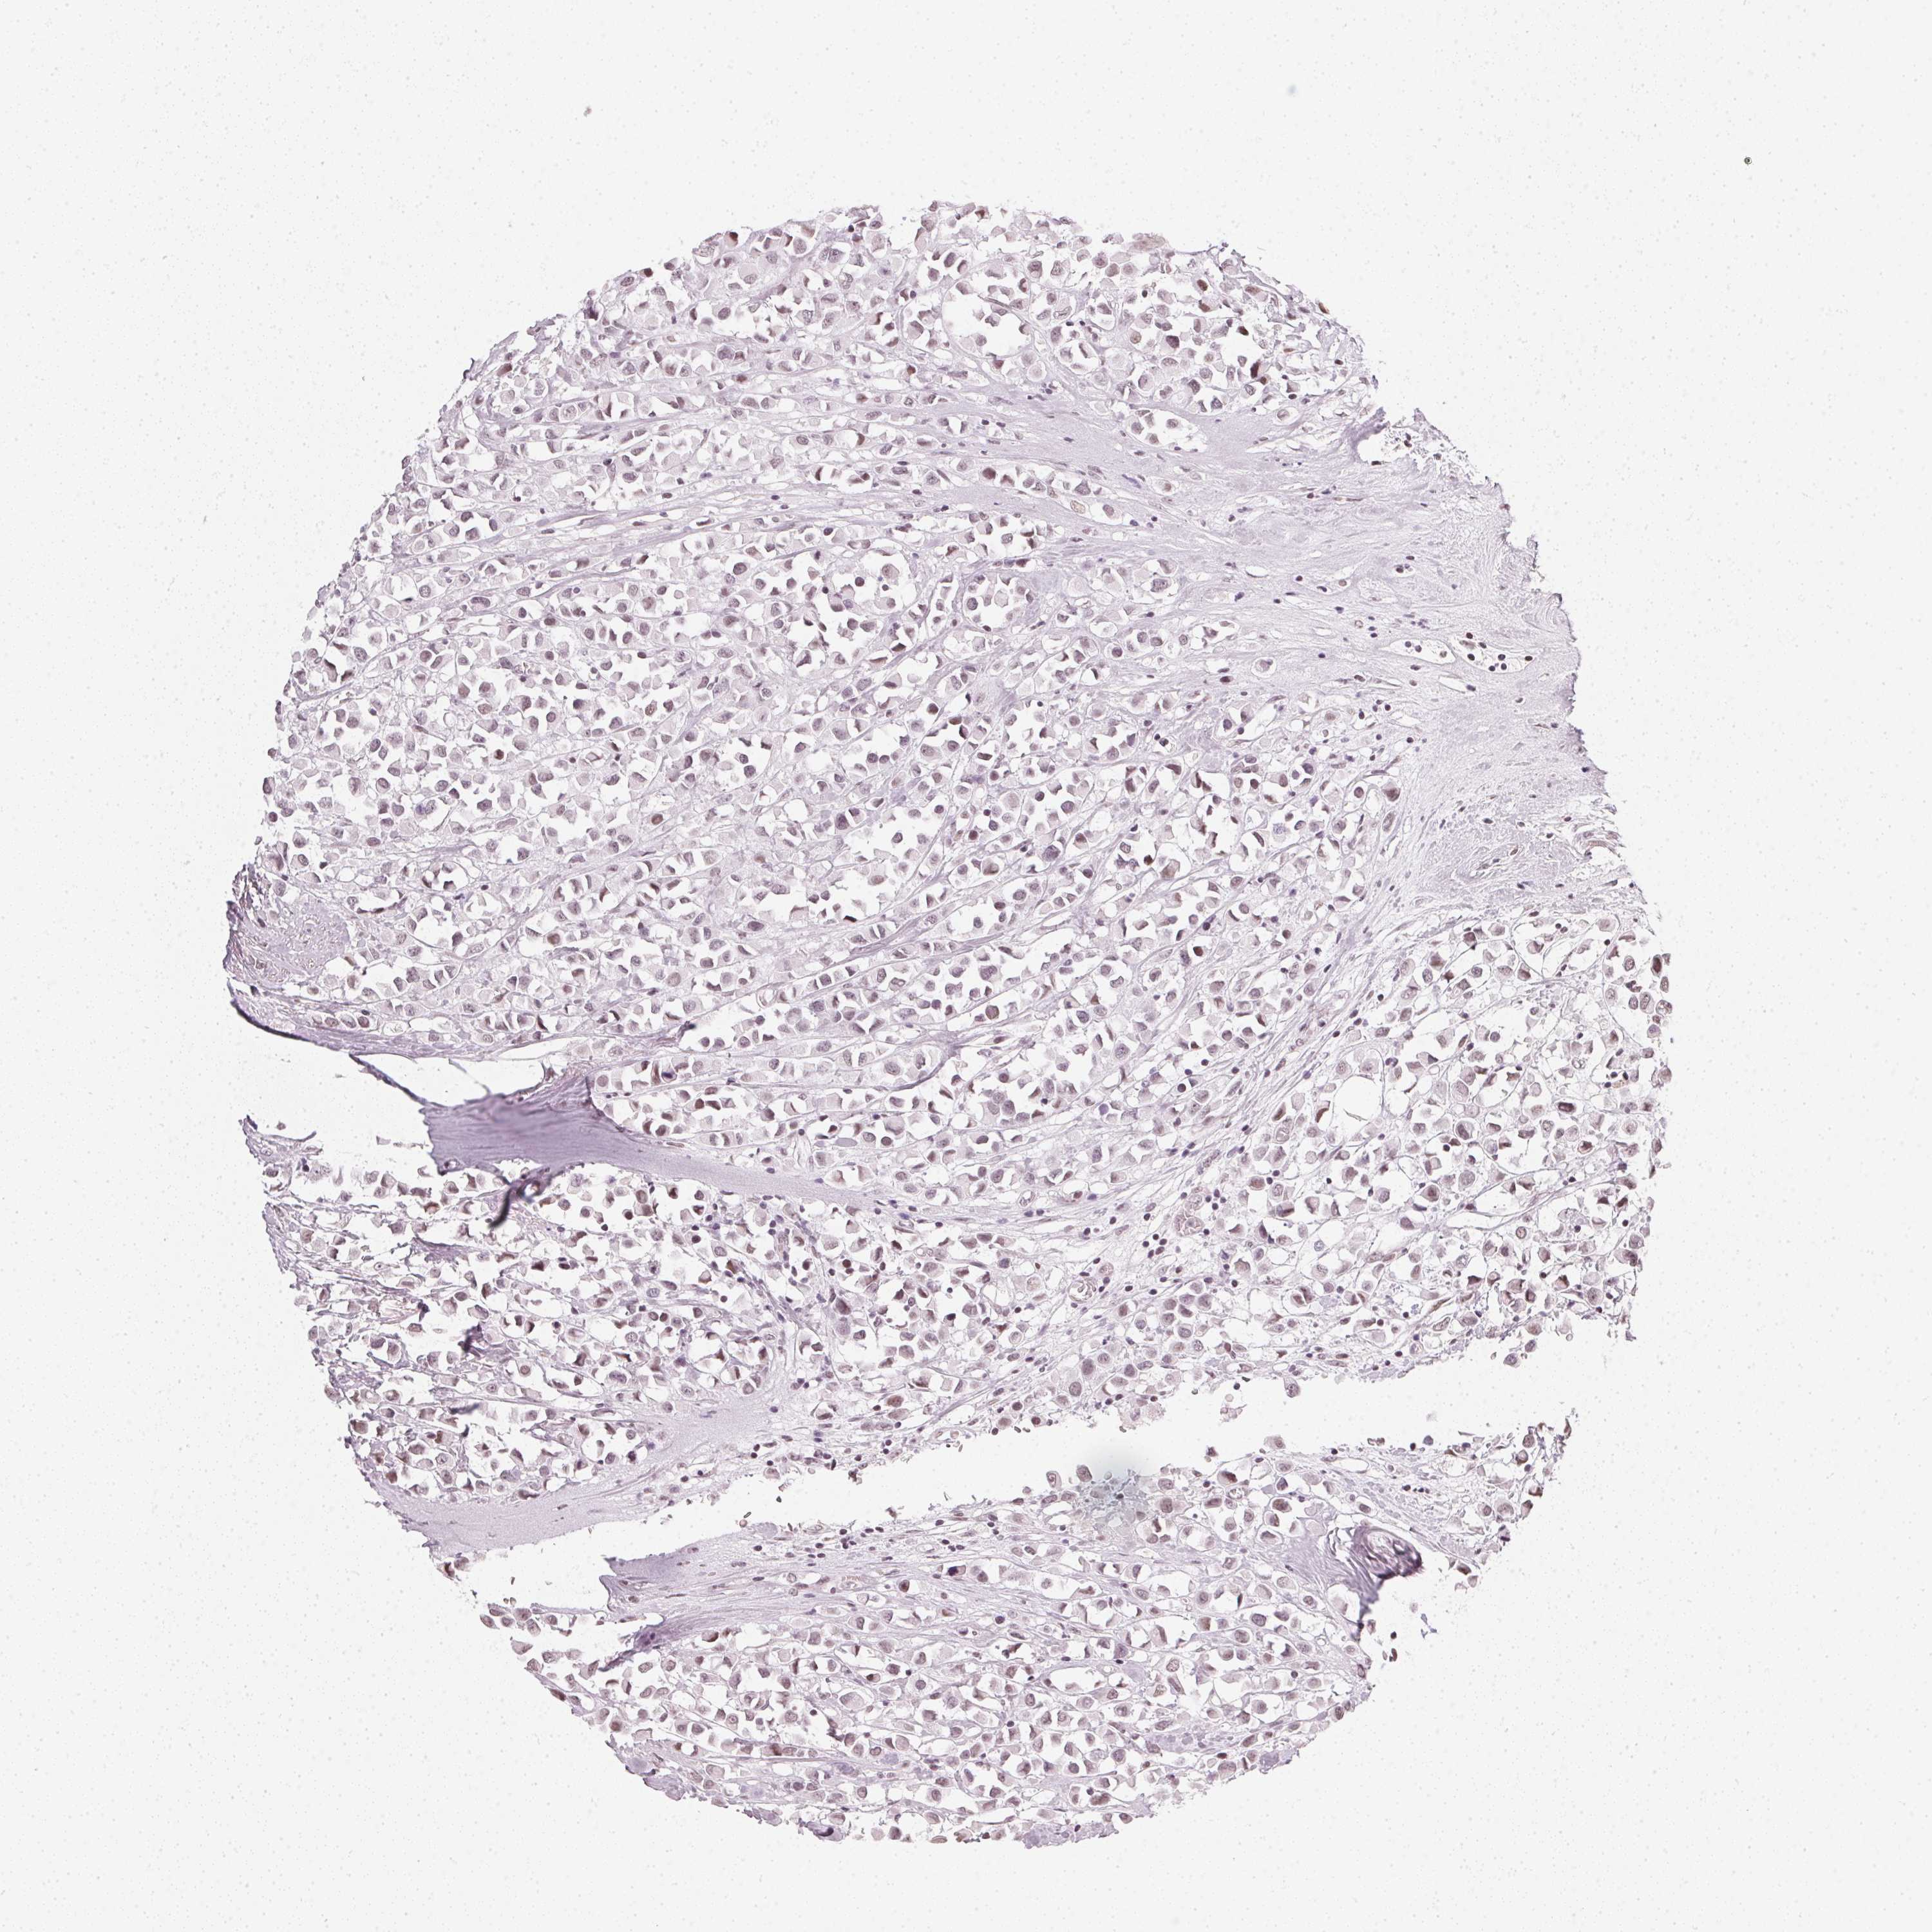

BRCA TCGA BRCA VALIDATION PROTEIN EXPRESSION

Breast cancer

Human cancer